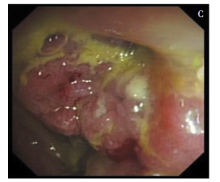

目的:探讨结肠鳞癌和腺鳞癌的临床病理学特征。方法:回顾性分析2例结肠鳞癌和2例结肠腺鳞癌患者的临床病理特征和预后。结果:4例患者中,男性1例,女性3例,年龄为29~76岁。2例伴血清糖类抗原19-9增高,分别为88.25 ng/mL和553.13 ng/mL;2例伴血清癌胚抗原增高,分别为116.39 U/mL和37.22 U/mL。3例患者的肿瘤发生于升结肠,1例发生于降结肠。镜下,4例鳞癌区域,肿瘤组织排列成不规则巢团状或片状,肿瘤细胞多角形或不规则形,细胞嗜酸异型,且表达P40和P63;2例腺鳞癌的腺癌区域,肿瘤组织排列成不规则腺管状或筛孔状,细胞核深染异型,且肿瘤细胞表达CAM5.2和CK20;3例表达P16。1例合并血吸虫感染。无患者感染人乳头瘤病毒,3例存在错配修复蛋白表达缺失,3例存在KRAS基因突变。中位随访期为42个月,1例患者于术后16.4个月死亡,其余3例存活,无复发。结论:鳞癌和腺鳞癌是肠癌极罕见的组织病理学类型,生物学行为不良,多伴错配修复蛋白表达缺失和KRAS基因突变。根治性手术切除可使患者获得良好预后。